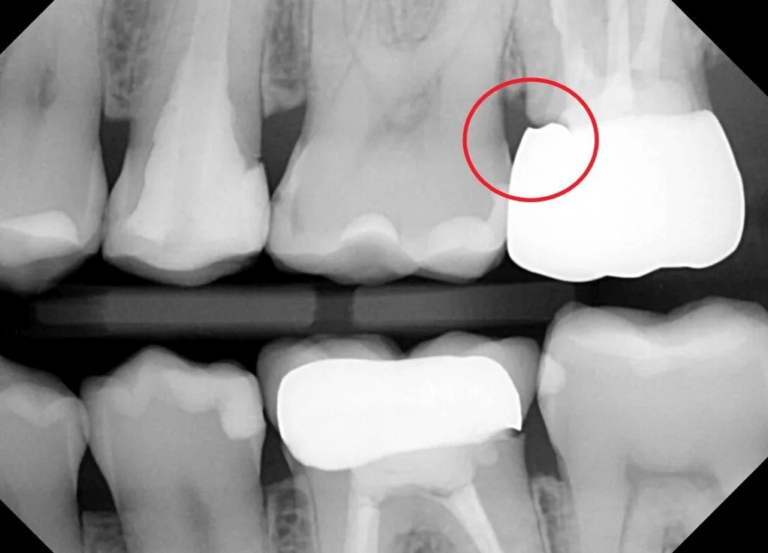

사진의 빨간 원 안을 보시면 크라운과 뿌리쪽에 틈이 있는걸 알 수 있습니다. 이 경우 문제가 됩니다. 치과에 방문하셔서 확인하시는게 좋습니다.(출처: https://atlasdental.ca/dental-crown-open-margin/)

③ 미세 틈, 접착 문제

크라운과 치아 사이 작은 틈으로 세균이 침투하면, 그 틈이 시림·염증의 원인이 됩니다.

시간이 지나며 틈 생김

시린 느낌이 점점 증가

→ 2차 문제로 발전 가능성

이 경우엔

크라운 적합 상태 확인이 필요합니다.